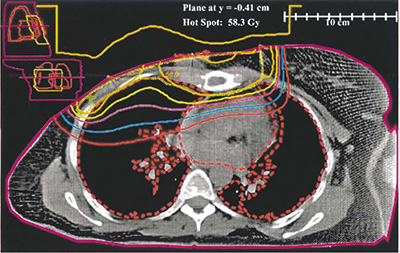

中等风险乳腺癌患者 术后胸壁放疗不改善预后

英国爱丁堡大学Kunkler等报告的针对1607例患者随访10年的结果显示,中等风险乳腺癌患者乳房切除术后胸壁放疗并未改善总生存和复发风险,研究结果不支持中等风险患者术后放疗。(N Engl J Med. 2025, 393: 1771.)